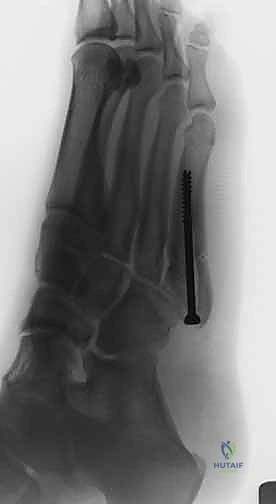

الدليل الجراحي الشامل: عملية التثبيت بالمسمار النخاعي الداخلي

عملية تثبيت كسر جونز بالمسمار النخاعي (Intramedullary Screw Fixation) هي جراحة دقيقة تتطلب مهارة استثنائية. وهي من التخصصات الدقيقة التي يتميز بها الأستاذ الدكتور محمد هطيف في صنعاء.

خطوات العملية الجراحية (خطوة بخطوة)

- الشق الجراحي الدقيق (Minimally Invasive): لا يقوم الدكتور هطيف بفتح شق كبير، بل يُحدث شقاً صغيراً جداً (حوالي 1 إلى 2 سم) عند قاعدة العظمة الخامسة لمشط القدم. هذا الشق الصغير يقلل من الألم بعد العملية ويسرع التئام الجرح ويحافظ على الشكل الجمالي للقدم.

- إدخال سلك التوجيه (Guide Wire): تحت توجيه الأشعة السينية المباشرة في غرفة العمليات، يتم إدخال سلك معدني رفيع جداً ليمر عبر الكسر وصولاً إلى النخاع العظمي. هذه الخطوة تتطلب دقة متناهية لضمان أن السلك في المنتصف تماماً.

- التحضير والتوسيع (Drilling/Tapping): يتم استخدام مثقاب خاص مجوف يمر فوق سلك التوجيه لتوسيع القناة النخاعية وتجهيزها لاستقبال المسمار.

- إدخال المسمار التيتانيوم (Screw Insertion): يتم اختيار مسمار طبي من التيتانيوم (طوله وسمكه محسوبان بدقة لتناسب عظمة المريض). يتم إدخال المسمار ليربط بين جزئي الكسر، مما يولد قوة ضغط (Compression) تجعل حواف العظم متلاصقة تماماً، وهو السر وراء الالتئام السريع.

- الإغلاق التجميلي: يتم إغلاق الشق الصغير بغرز تجميلية، ووضع ضمادة معقمة وحذاء طبي لحماية القدم.